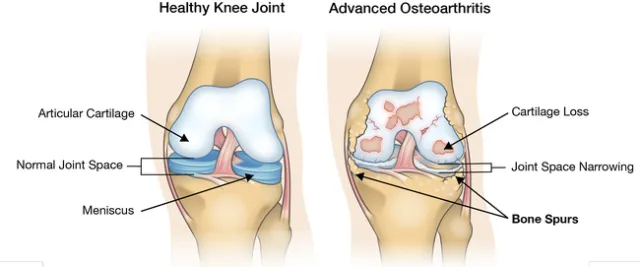

Did you know you have 209 bones in your body? The word bone in Greek is “osteon.” It is commonly used as a prefix to refer to issues of the bones. Each bone has two ends and where they meet another bone, that area is is called a joint. In Greek, joint = “arthro.” If joints are overused they become inflamed. The Latin suffix for inflammation = “itis.” Each joint can suffer from wear and tear with inflammation pain and that is called arthritis. More specifically, it would be osteo-arthritis.